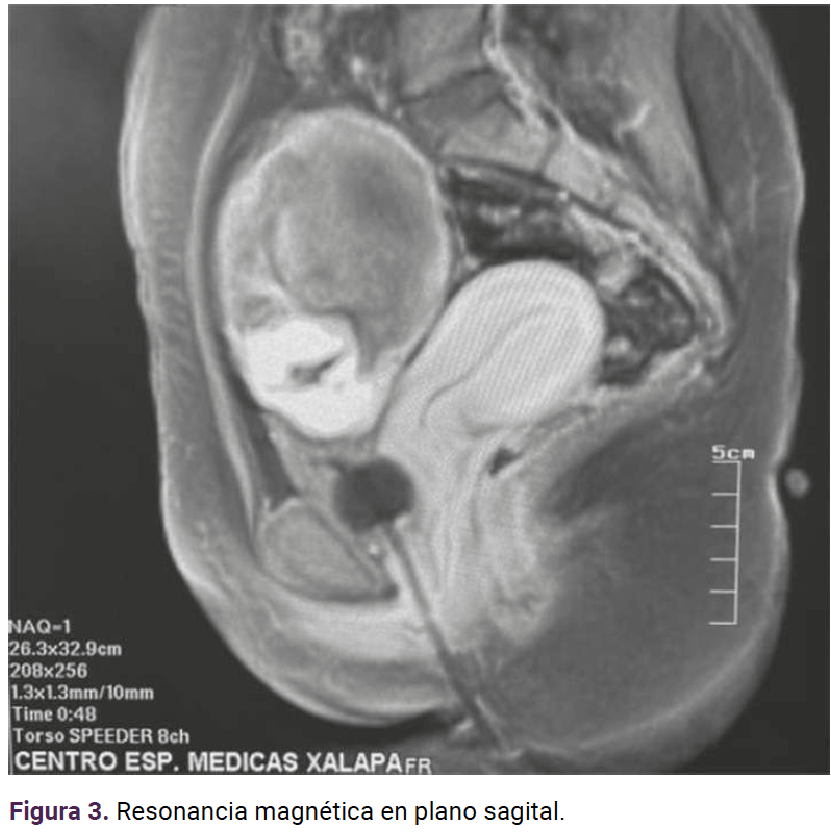

La resonancia magnética determinó el sitio de implantación: en el hueco pélvico el útero se observó en situación y morfología habitual, con diámetros máximos de 75 x 80 x 45 mm. El miometrio aparentemente homogéneo; el endometrio central, lineal e hiperintenso con espesor de 2.1 mm. El cuello uterino se apreció con adecuada intensidad de señal y sin alteraciones aparentes. En el ovario derecho se visualizó una imagen heterogénea, con estructuras fetales y la placenta con realce al paso del contraste, adherida a la pared posterior. Hubo zonas en el peritoneo parietal donde no se logró delimitar su interfaz (109 x 68 mm). El anexo izquierdo se encontró con morfología e intensidad de señal adecuadas. En la cavidad abdominal no se observaron líquido libre ni colecciones. Figuras 3 y 4

Figura 3. Resonancia magnética en plano sagital.

Si bien el ultrasonido transvaginal es un método auxiliar simple y reproducible para diagnosticar el embarazo ectópico, se menciona que el índice de diagnóstico acertado preoperatorio del embarazo ovárico con este método es solo del 18%.7 Algunos estudios reportan la utilidad de la resonancia magnética cuando los informes del ultrasonido transvaginal son insuficientes o inconclusos, sobre todo para diagnósticos específicos de embarazos ectópicos infrecuentes o complicados.11 Los hallazgos incluyen: estructuras parecidas a un saco gestacional, hematoma anexial o abdominal, dilatación tubárica debida a hemosalpix y realce de la pared tubárica.11 Cuando se carece de este recurso y no se consigue delimitar adecuadamente la localización precisa del embarazo extrauterino, lo conducente es la resonancia magnética.11